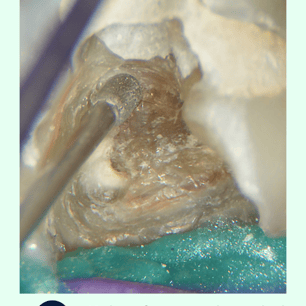

Localización y Remoción de

Calcificaciones: Se utilizan instrumentos especiales, como limas ultrasonicas, para localizar y remover las calcificaciones.

Instrumentos: Explorador dental, radiografías, limas ultrasonicas, materiales de sellado.